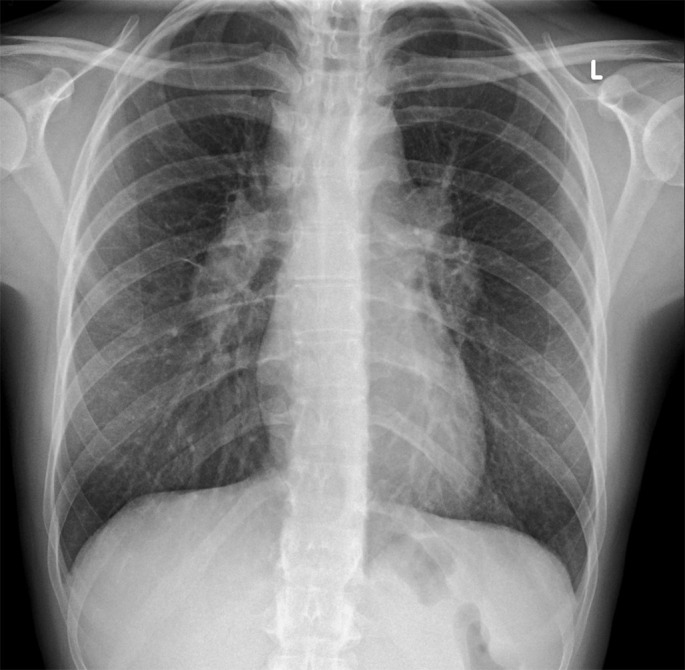

A 40-year-old woman begins to have breathing difficulties after a history of ophthalmological issues. She then has a complex and complicated clinical course with multiple interesting diagnoses and treatments, with much to be learnt along the way. https://bit.ly/4gIolF8.